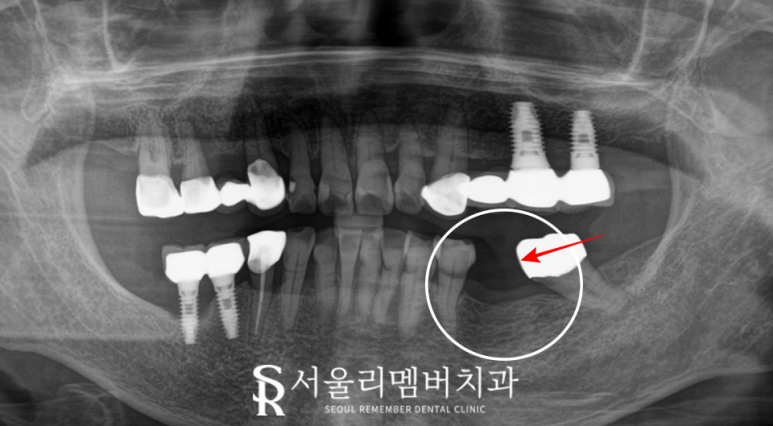

하악 좌측 첫 번째 큰 어금니가

없는 상태로

잇몸이 이미 아물어 있고

골폭이 좁아져있는 것을 보아

아마 이가 빠진지 꽤 오래되신 거 같습니다.

자연치가 상실되면

그자리의 뼈가 퇴축되면서 나타나는 현상이죠.

또한 엑스레이를 찍어

임플란트를 할 수 있는 뼈 상태인지 살펴보니,

다행히 치조골의 높이도 높고

염증소견도 없어서

이 정도면 당일 즉시 식립도 가능합니다.